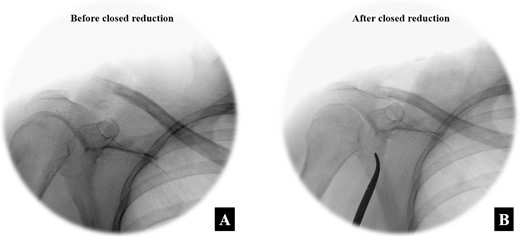

A second Nice knot was placed beside the first Nice knot to further secure and preserve the fracture alignment. The intra-operative fluoroscope images between before the closed reduction and after the closed reduction with the Nice knot technique are shown in Fig. 6A and B. Closure of the clavicular fascia and the anterior deltoid musculature was done with a Vicryl No.1 suture and the skin was closed using Nylon No.3.

The intra-operative fluoroscope images between (A) before the closed reduction and (B) after the closed reduction with the Nice knot technique in the anteroposterior view.